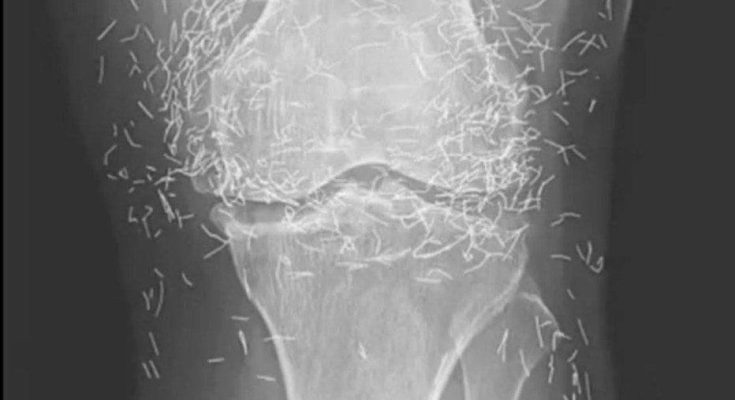

Years later, when doctors took X-rays to evaluate her knee condition, they weren’t prepared for what appeared on the images. Her knees were filled with dozens of bright, metallic flecks — tiny needles embedded deep within the joint area.

The findings were later documented in a case published by the New England Journal of Medicine.

Beyond inflammation, the needles created another problem: imaging complications. Metal objects can obscure parts of the anatomy on X-rays, making it harder for doctors to clearly assess joint damage or disease progression.